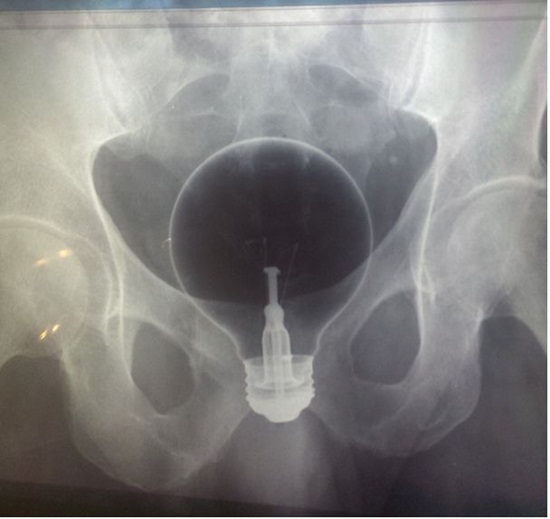

หลอดไฟ !!!

ขวดแชมพู